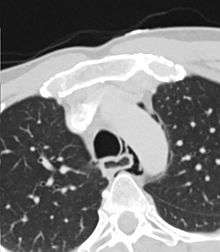

The diagnosis of Boerhaave's syndrome is suggested on the plain chest radiography and confirmed by chest CT scan. The initial plain chest radiograph is almost always abnormal in patients with Boerhaave's syndrome and usually reveals mediastinal or free peritoneal air as the initial radiologic manifestation. With cervical esophageal perforations, plain films of the neck show air in the soft tissues of the prevertebral space.

Hours to days later, pleural effusion(s) with or without pneumothorax, widened mediastinum, and subcutaneous emphysema are typically seen. CT scan may show esophageal wall edema and thickening, extraesophageal air, periesophageal fluid with or without gas bubbles, mediastinal widening, and air and fluid in the pleural spaces, retroperitoneum or lesser sac.